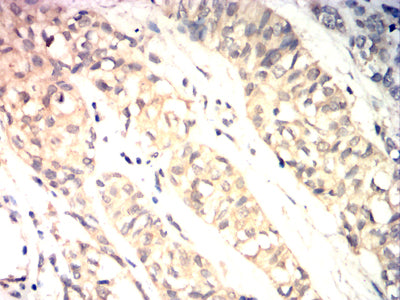

分类: 科研抗体货号: 32216别名: FRA应用: IHC,FCM反应种属: Human